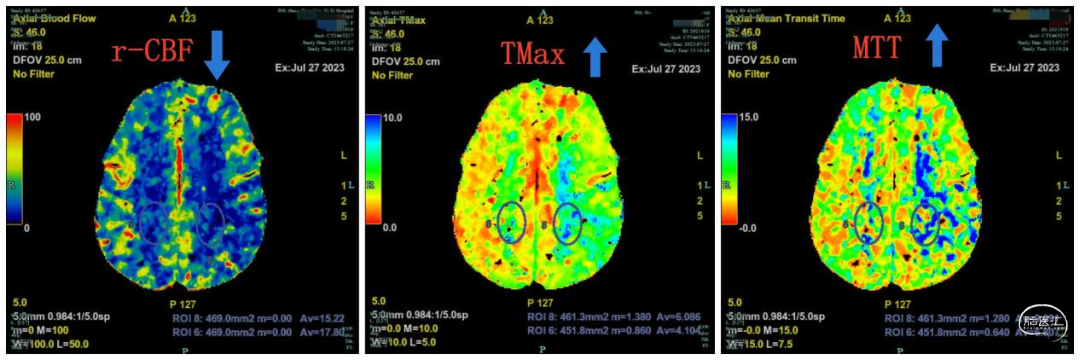

脑血流灌注检查:(图2)。MR检查未见明显脑梗死等改变。

图2. (左侧中动脉供血区r-CBF↓ ,TMax↑,MTT↑)